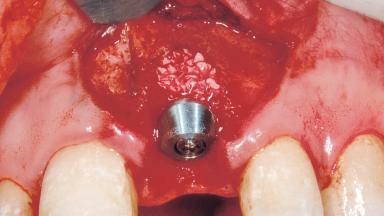

Immediate Placement of an Implant in a Maxillary Left Central Incisor Site

A 33-year-old female patient presented with an upper left central incisor that required extraction after a failed endodontic therapy. The tooth had been traumatized when the patient was a teenager and had undergone several endodontic treatments, including two apicectomy procedures. The patient was in good health and did not smoke. Clinical examination showed that the patient had a high lip line. In full smile, the gingival margins of the upper teeth were visible to the first molars. The gingival margins of central incisors 11 and 21 were only just showing. Examination of tooth 21 confirmed that the tooth was mobile and had hypererupted by 1 mm.

Placement Protocol Immediate implant placement

Socket Integrity Damage to one or more bone walls

Bone Volume Damage to one or more socket walls